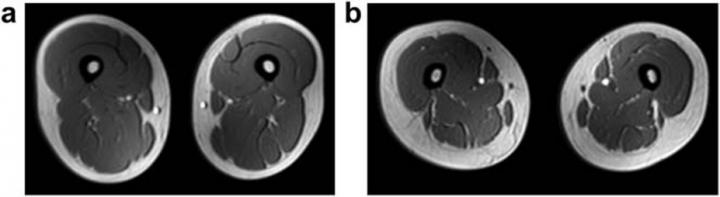

image: Representative magnetic resonance images of the femoral region in a female subject without non-alcoholic fatty liver disease (NAFLD) (a) and that in a female subject with NAFLD (b). The NAFLD subject had greater s.c. fat thickness, decreased muscle cross-sec-tion, and marbled muscles (steatosis) on the images.

The researchers found that of the male and female patients, one quarter of the members of each group had non-obese NAFLD. Surprisingly, these patients had lower skeletal muscle mass and muscle strength (pre-sarcopenia) compared with obese NAFLD patients. Although afflicted by fatty liver disease, there was only a modest increase in liver fat accumulation and insulin resistance (a precursor to diabetes and often associated with NAFLD) in non-obese NAFLD patients compared with obese NAFLD patients. This was further corroborated by the fact the visceral, or belly, fat was overall low in non-obese NAFLD patients. Interestingly, fat accumulation in muscles was more common among women. An integrated analysis of the data showed that liver fat accumulation in non-obese NAFLD was mainly dependent on visceral fat content, leptin (a hormone produced in visceral fat tissue and that induces inflammation), myostatin (a protein produced by skeletal muscle to suppress muscle regeneration) and HbA1c (a blood marker for how well the body manages blood sugar levels in the long term).